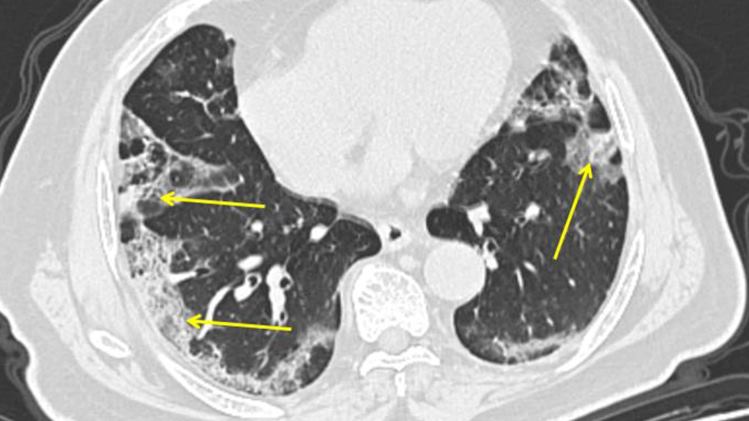

Vilson kaže da postoje dokazi da pneumonija uzrokovana Covid-19 može biti posebno teška, te da slučajevi koronavirusne upale pluća pogađaju kompletno pluća, umjesto samo malih dijelova.